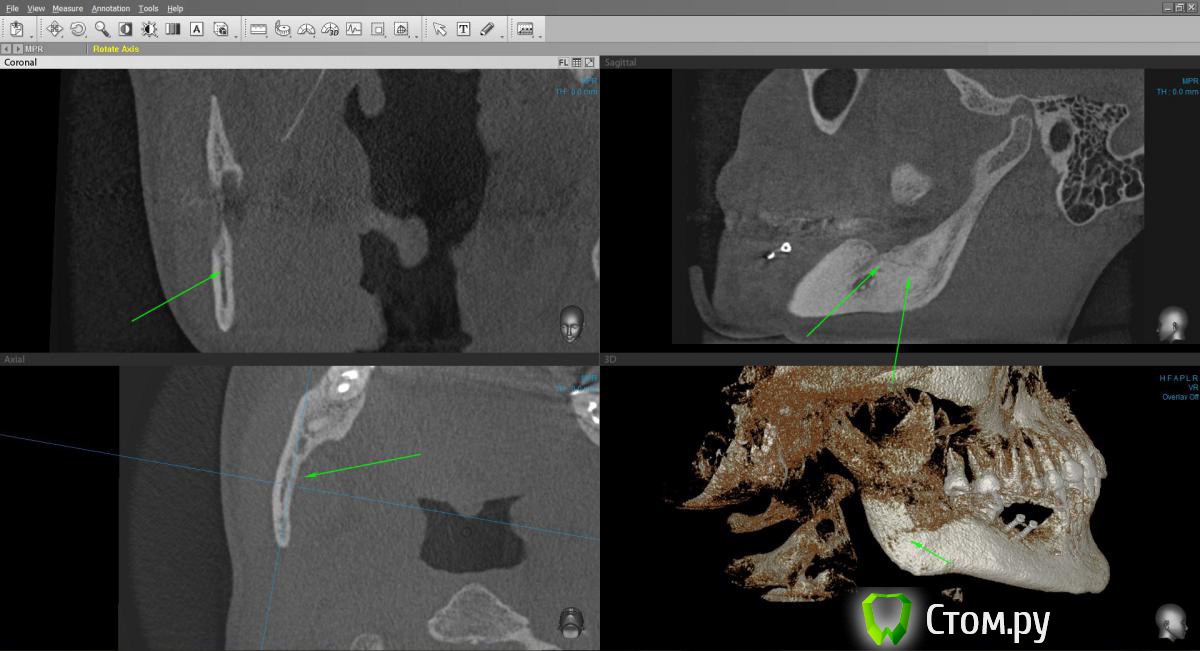

Марьяна Опубликовано 22 ноября, 2014 Автор Поделиться Опубликовано 22 ноября, 2014 Попробую. В программе конечно проще поймать линии переломов.Ну вот ..в области конкретно ветви: Ссылка на комментарий

kriokov Опубликовано 23 ноября, 2014 Поделиться Опубликовано 23 ноября, 2014 Хорошо, вот: Марьяна Александровна, по панораме.Мне кажется нет перелома нижней челюсти в обл угла и в обл ветви. Но это мое личное мнение и я его попытаюсь обосновать.Зеленая стрелка показывает на место забора блокажелтая на линию восходящей части венечного отростка-- там нет непрерывностисиняя стрелка -- ветвь, линия может быть и артефактом связанным с забором блока, если он был значительным по протяжению.Мне кажется , Вам надо списываться с доктором, ( напомнить ему , что Вы стоматолог, еще раз без обиняков изложить все вопросы которые Вас тревожат), осмотр, и решать , что дальше делать. http://www.imageup.ru/img214/1954483/maryana.jpg Ссылка на комментарий

Марьяна Опубликовано 23 ноября, 2014 Автор Поделиться Опубликовано 23 ноября, 2014 (изменено) Если и был перелом, то без смещения и уже зажил...отправьте дайкомы Дмитрию Рогацкину.Да, зажил, и слава Богу. Отправлять дайкомы Рогацкину смысла нет. Он скажет, то, что есть. А есть двойной перелом. Я сама есть консультант по 3D КТ, :-) С Иваном Морозовым , который представляет Рогацкина у нас в Новосибе мы уже пообщались и в Анатомаже он и сделал мне одну из нарезок. И рентгенолог, которго хвалит Рогацкин, тоже в курсе)Смещение , кстати, есть, небольшое, дистально.Это видно по дистальному контуру ветви.Почему я выношу на общее обсуждение свою историю? Ну мне обидно, да. Обидно, что со мной так обошлись коллеги. Что по необъективным причинам, без уведомления был изменен план лечения. Что скрыли истинную причину, по которой срочно прекратили операцию и отложили вторую на две недели. Позиция лечащего врача сейчас убивает наповал. Я даже по-началу засомневалась в своей компетентности, увидев повторное КТ и его резюме по нему.Я ещё хотела написать вот что. Суть моего поста здесь. По факту..я имею право предьявить претензию, но не хочу. Слава Богу, что все обошлось без серьезных осложнений. Что не было остеомиелита, что не случилось явного смещения, несмотря на то, что перелом не был шинирован и т.д. и .т.п.Я оскорблена поведением врача. У нас у всех есть свое маленькое кладбище и мы знаем и помним о всех своих ошибках. Но надо уметь признавать ошибки и исправлять. И если именитый врач ведет себя, как нашкодивший пацан...если между коллегами такое вот отношение, страшно за пациентов, которые вообще не в теме.В общем...лозунг какой-то получился) Уважайте своих пациентов и друг друга. Изменено 23 ноября, 2014 пользователем Марьяна 5 Ссылка на комментарий